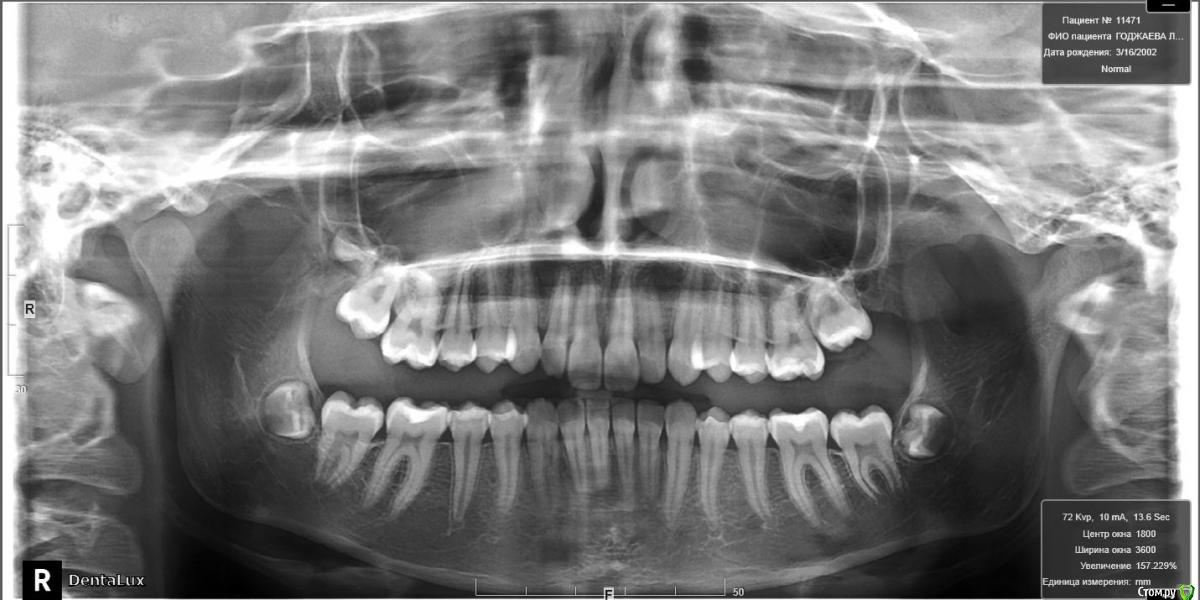

Пациентка 14 лет. Было принято решение лечить без удаления, тк. профиль не позволяет да и ретропозиция нч. Лечение идет. Я назначила ранние эластики слабые, на 17/25 нити на вч и 18 нити на нч. по 2 классу короткие 3,4-4,5. Пациентка пришла через месяц жалуется на щелканье челюсти во время ношения эластиков и сразу после их снятия. Т.е. если открывает рот, то челюсть скачкообразно двигается и щелчками. Последние 2 недели, когда много говорит, то вообще стала заедать. Это она так сказала. После отмены эластиков (страшно), через неделю пришла, рот открывает ровно, без девиации, щелчков нет. Вопрос: почему щелкает и что с этим делать? По поводу прикуса, посоветуйте, пожалуйста, как нормализовать? Аппарат типа гербста? может ей твинблок сделать? Эластики? К сожалению другими методами я пока что не владею. Спасибо, очень жду ваших советов.

Конечно, через интеонет трудно ответить, ведь щелчки бывают разные (в начале фазы открывания, в конце, в начале фазы закрывания, в конце закрывания? То есть если у нее смещена головка кзади ппи щакрытом рте, то при открывании у нее сразу должен быть щелчок (головка догнала диск), пожевала .., потом во время закрытия в самом конце опять щелчок (головка съехала с диска и стала в свое привычное положение). Это обычная картина при втором классе. Несьемные аппараты не будут давать уходить челюсти назад, щелчков быть не должно. После снятия аппарата зафиксируете новое положение челюсти бугорками антагонистов

Иными словами МРТ ВНЧС (чтобы не гадать), достаточно интересные заключения приходят уже лет в 15-16.